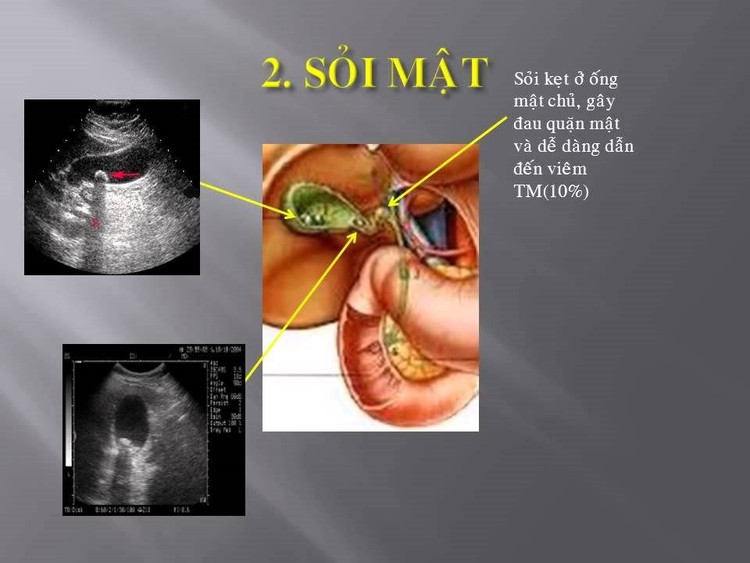

Sỏi túi mật phát hiện rất đơn giản nên mọi người cần chú ý để điều trị kịp thời, ngăn ngừa các biến chứng nguy hiểm. Hiện theo thống kê thì chỉ có khoảng từ 10-20% bệnh nhân có bệnh sỏi mật từ lúc phát hiện ra bệnh tới lúc có triệu chứng là sau 5-20 năm. Còn khi triệu chứng của bệnh, tức là có biến chứng rồi mới đi viện là tình trạng khá phổ biến của những người dân bị mắc bệnh sỏi mật.

Bệnh sỏi túi mật phát hiện rất đơn giản qua siêu âm và làm một số xét nghiệm cận lâm sàng. Nếu người dân thấy đau bụng, đặc biệt đau vùng gan, sốt, có dấu hiệu vàng da… thì cần phải đến cơ sở y tế thăm khám. Nếu người dân chủ quan, để bệnh trong tình trạng nặng sẽ dẫn tới nhiều biến chứng như viêm hoại tử túi mật hoặc sỏi rơi vào đường mật gây biến chứng viêm tụy cấp, tắc mật cấp.